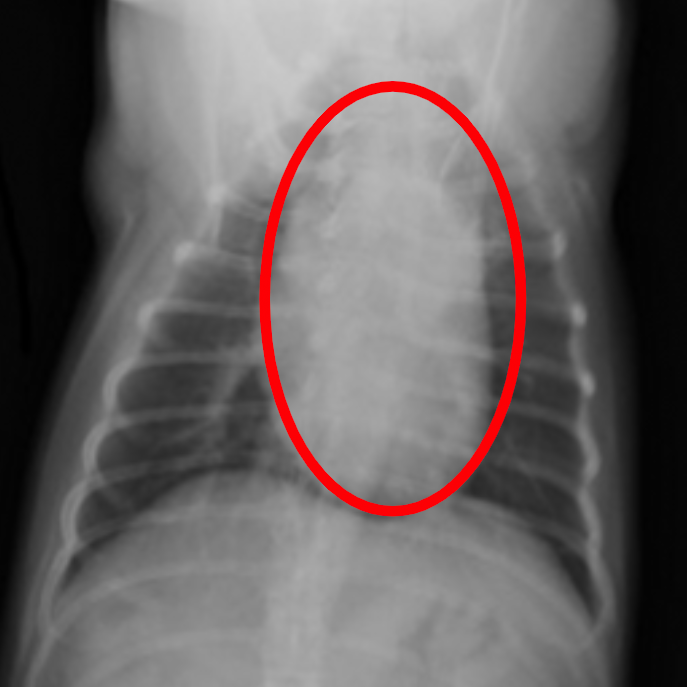

レントゲン検査

心臓の形や大きさ、肺、血管の太さのチェックをします。

肥大した猫の心臓の

レントゲン